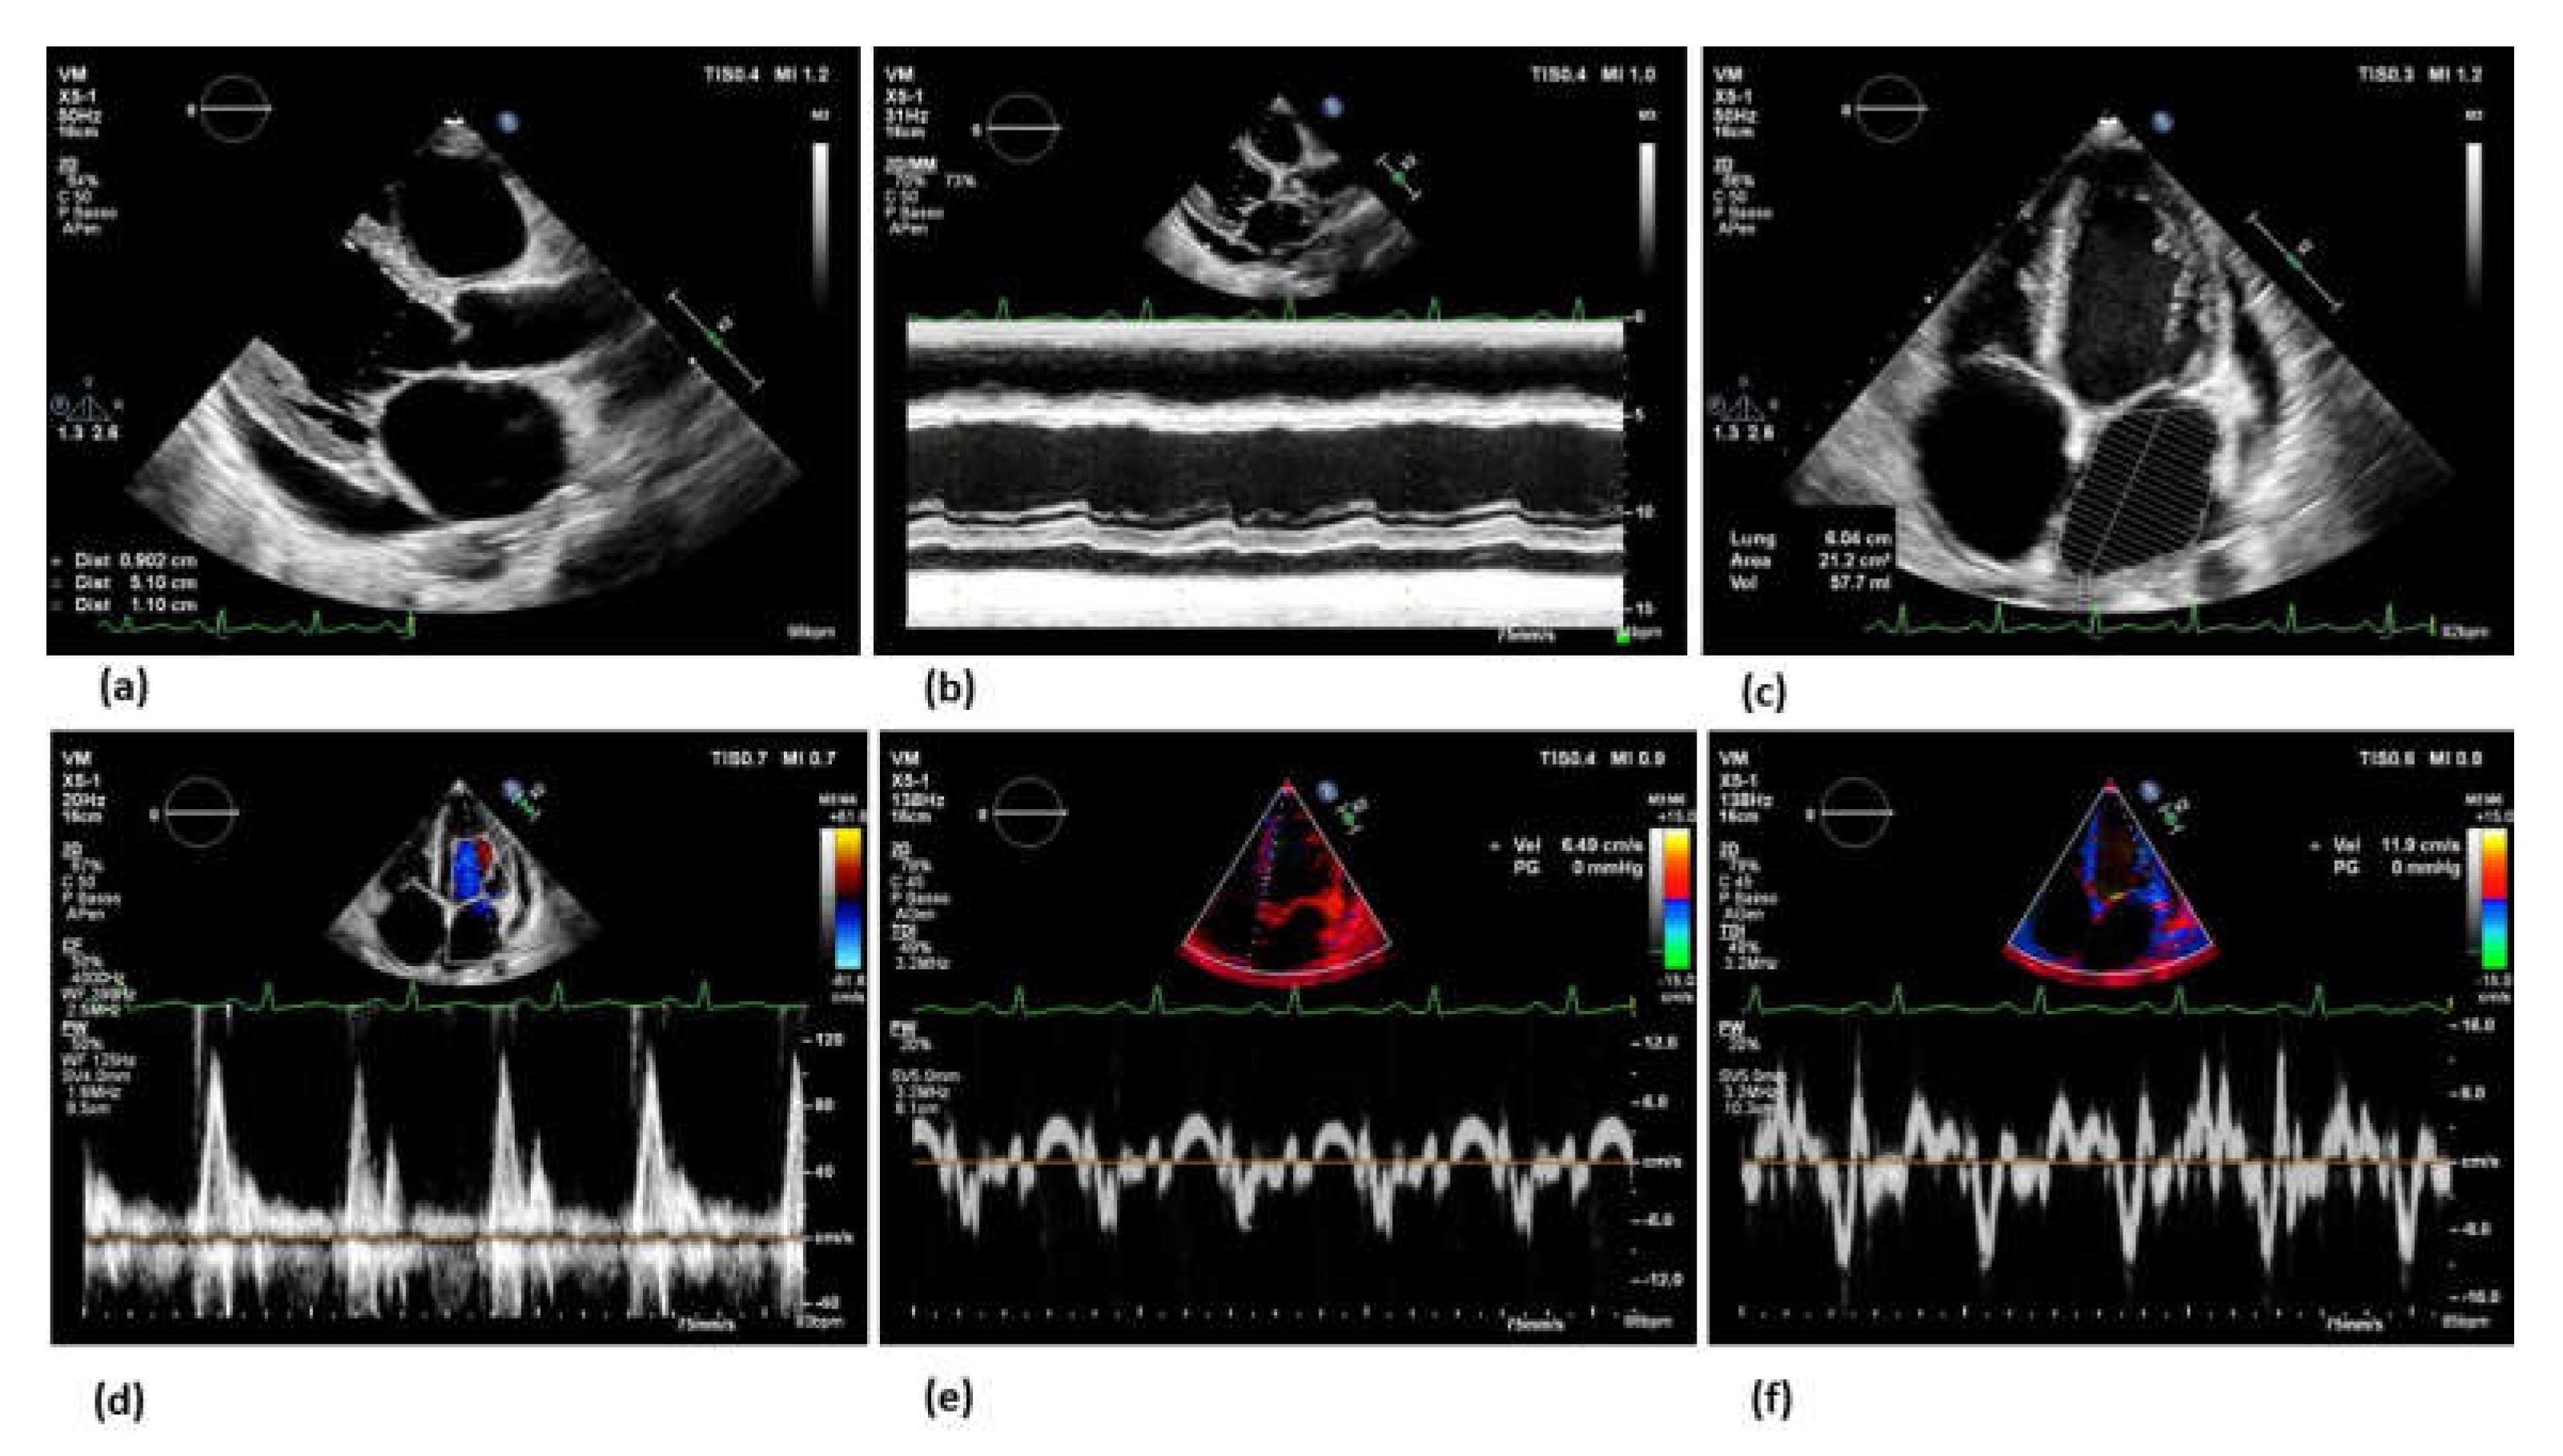

- Hassanin, N.; Alkemary, A. Early Detection of Subclinical Uremic Cardiomyopathy Using Two-Dimensional Speckle Tracking Echocardiography. Echocardiography 2016, 33, 527–536. [Google Scholar] [CrossRef] [PubMed]

- Krishnasamy, R.; Isbel, N.M.; Hawley, C.M.; Pascoe, E.M.; Leano, R.; Haluska, B.A.; Stanton, T. The association between left ventricular global longitudinal strain, renal impairment and all-cause mortality. Nephrol Dial Transplant 2014, 29, 1218–1225. [Google Scholar] [CrossRef] [PubMed]

- Frea, S.; Pidello, S.; Bovolo, V.; Iacovino, C.; Franco, E.; Pinneri, F.; Galluzzo, A.; Volpe, A.; Visconti, M.; Peirone, A.; et al. Prognostic incremental role of right ventricular function in acute decompensation of advanced chronic heart failure. Eur J Heart Fail 2016, 18, 564–572. [Google Scholar] [CrossRef]

- Maeder, M.T.; Holst, D.P.; Kaye, D.M. Tricuspid regurgitation contributes to renal dysfunction in patients with heart failure. J Card Fail 2008, 14, 824–830. [Google Scholar] [CrossRef]

- Pellicori, P.; Carubelli, V.; Zhang, J.; Castiello, T.; Sherwi, N.; Clark, A.L.; Cleland, J.G. IVC diameter in patients with chronic heart failure: relationships and prognostic significance. JACC Cardiovasc Imaging 2013, 6, 16–28. [Google Scholar] [CrossRef]

- Cowie, B.; Kluger, R.; Rex, S.; Missant, C. Noninvasive estimation of left atrial pressure with transesophageal echocardiography. Ann Card Anaesth 2015, 18, 312–316. [Google Scholar] [CrossRef]

- Park, J.H.; Marwick, T.H. Use and Limitations of E/e' to Assess Left Ventricular Filling Pressure by Echocardiography. J Cardiovasc Ultrasound 2011, 19, 169–173. [Google Scholar] [CrossRef]